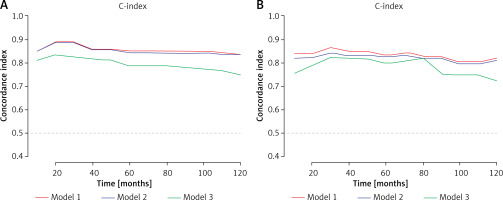

Accuracy of the LMR-SSIGN-MAPS model compared with other models

The accuracy among the LMR-SSIGN-MAPS (model 1), SSIGN-MAPS (model 2), and SSIGN score (model 3) was compared using Harrell’s C-index. The Harrell’s C-index for LMR-SSIGN-MAPS were 0.854 (95% CI: 0.815–0.893) and 0.848 (95% CI: 0.807–0.889) comparing with SSIGN scores of 0.782 (95% CI: 0.777–0.787) and 0.772 (95% CI: 0.699–0.845) in the training and validation cohorts, respectively (Table IV, Figures 4 A, B). The Kaplan-Meier survival analysis revealed that the stratified groups, based on the LMR-SSIGN-MAPS model, have significant differences in predicting DFS in localized ccRCC. Higher LMR-SSIGN-MAPS score was associated with poor DFS in the overall cohort (p < 0.0001) (Figure 4 C). The calibration curves displayed that the predicted probabilities of 1.5-year DFS (Figures 4 D, E) in the training cohort and 1.5-year DFS (Figures 4 F, G) in the validation cohort matched well with the observed probabilities.

Figure 4

Accuracy of LMR-SSIGN-MAPS model compared with other models. A – Use the c-index to compare the LMR-SSIGN-MAPS model with the other models in the training cohort; B – Use the c-index to compare the LMR-SSIGN-MAPS model with the other models in the validation cohort. (model 1, LMR-SSIGNMAPS score; model 2, SSIGN-MAPS score; model 3, SSIGN score)

DFS – disease-free survival, LMR – lymphocyte to monocyte ratio, C-index – Harrell’s concordance (c)-index, SSIGN – the Mayo Clinic Stage, size, grade, and necrosis score, MAPS – Mayo adhesive probability score.